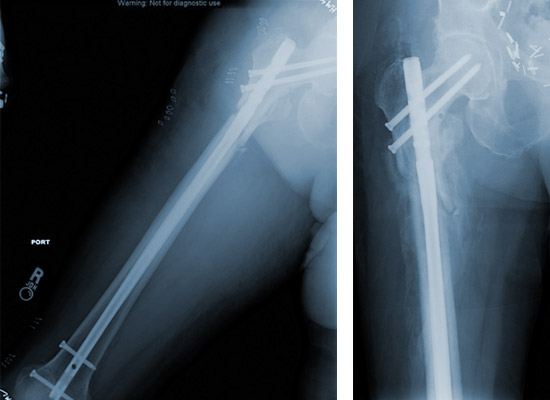

Femoral Recon Nail Specification, Uses, Sizes and Surgical Techniques

Femoral Recon Nail is designed to help treat various fractures of the femur. Different nails are available to be placed through the tip of the Greater Trochanter. Screws are placed through the nail to secure the implant in place and maintain length and alignment while healing occurs. The nails have multiple screw holes in the proximal body to allow surgeons to address different fracture types. Proximal and distal slots allow for compression or dynamization across a fracture.

Your surgeon will push the femoral nail down the inside of the bone, either through a cut on the side of the hip or on the front of the knee. The nail goes across the break and holds it in position. The nail is held in the bone by locking screws that pass through holes in the nail. If you have an open fracture, your surgeon will clean the skin wound thoroughly during the operation to reduce the risk of infection. If the skin is badly damaged, you may also need one or more plastic surgery operations. At the end of the operation, your surgeon will close the skin with stitches or clips.